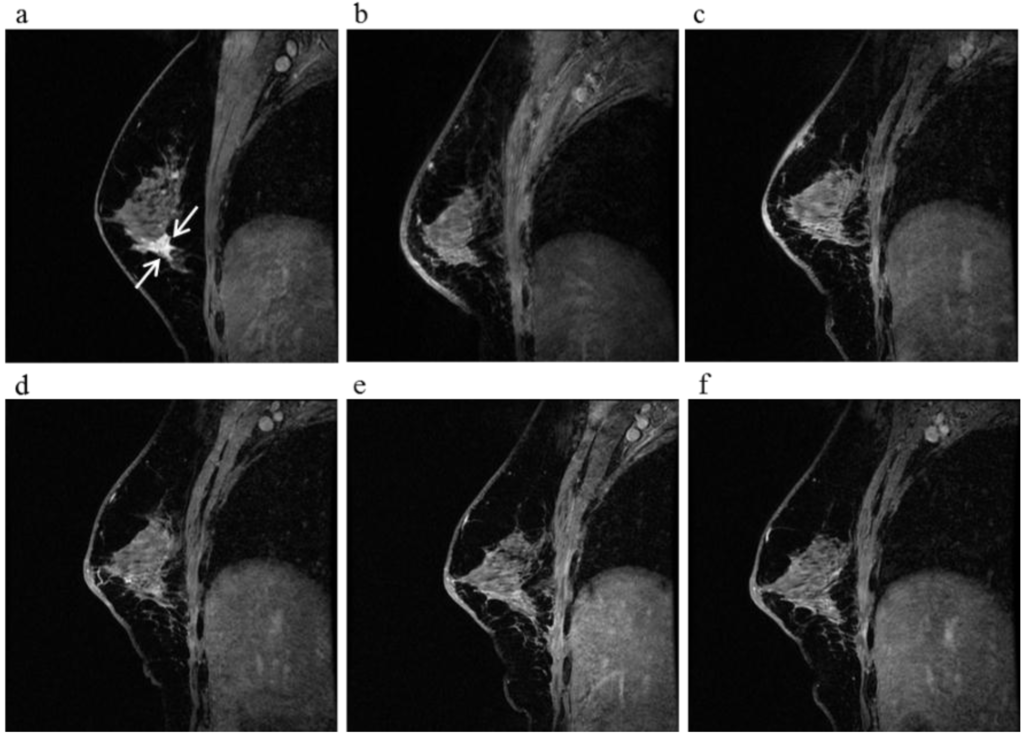

Figure 5.

A 60-year-old female (case 4 in Table 1, Table 2 and Table 3) with right breast cancer (cT1cN0M0). CE breast MRI (a) revealed a breast tumor before KORTUC II therapy, the region of tumor was 18 mm (arrows); After KORTUC II, no recurrence was identified on CE breast MRI ((b): 5 month; (c): 17 month; (d): 29 month; (e): 41 months; (f): 53 months).